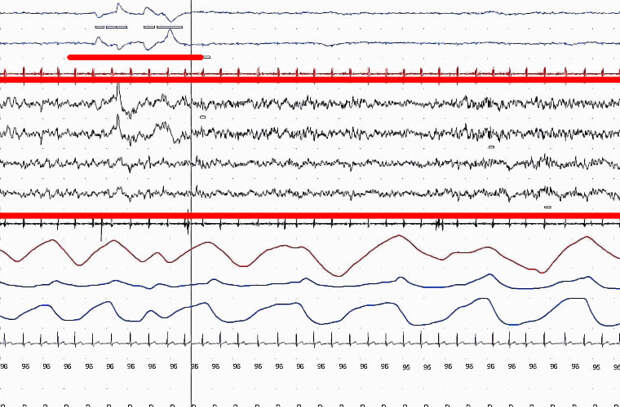

Электроэнцефалограмма и фаза быстрого сна (подчеркнута)

А 32 дня, проведенные в Мамонтовой пещере Кентукки, в условиях отсутствия естественного света и сигналов извне, легли в основу изучения влияния окружающей среды на биологические ритмы человека. Клейтман использовал в качестве подопытного не только себя, но и свою семью, родственников и знакомых. Он вел подробный дневник сна и бодрствования своих дочерей от момента рождения и до 18 лет, а фазу быстрого сна впервые зафиксировал в 1952 году — при наблюдении за сыном своего ассистента.